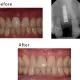

case-studies Case #3 This patient lost his teeth because of periodontal disease. They were restored with implant-supported crowns.February 26, 2024/by Rich https://sunnyvaledentalspecialty.com/wp-content/uploads/2018/08/blog2.jpg 512 614 Rich https://sunnyvaledentalspecialty.com/wp-content/uploads/2017/03/logo.png Rich2024-02-26 12:31:502024-05-02 11:09:46Case #3